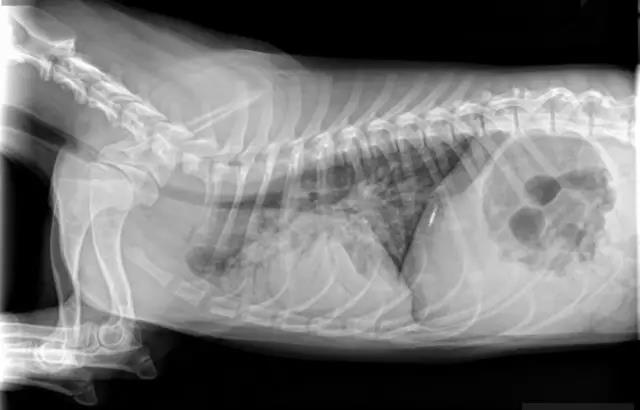

肺炎

狗狗肺炎发生原因比较复杂,一般来讲,症状是狗鼻腔会出现大量黄色分泌物,检查方法除了血液检查及X光之外,细菌的培养及药物敏感测试是有效的选择药物方式。